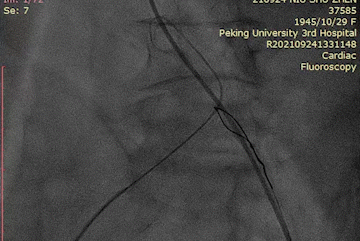

左冠造影

横位心顺利跨瓣